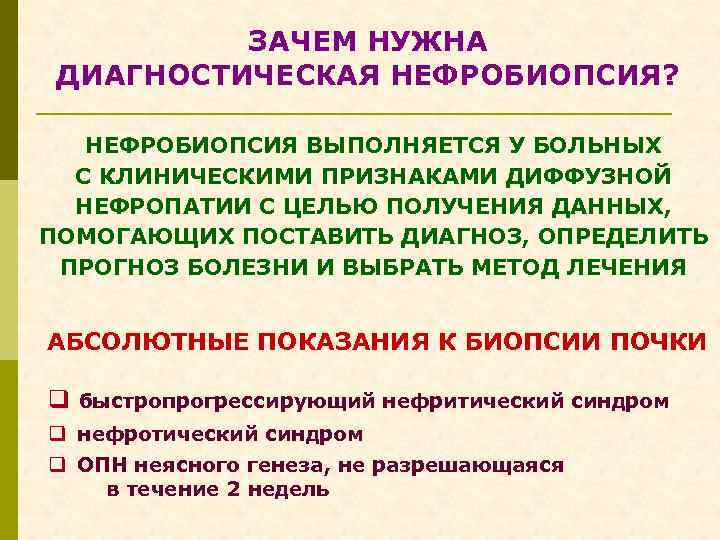

ЗАЧЕМ НУЖНА ДИАГНОСТИЧЕСКАЯ НЕФРОБИОПСИЯ? НЕФРОБИОПСИЯ ВЫПОЛНЯЕТСЯ У БОЛЬНЫХ С КЛИНИЧЕСКИМИ ПРИЗНАКАМИ ДИФФУЗНОЙ НЕФРОПАТИИ С ЦЕЛЬЮ ПОЛУЧЕНИЯ ДАННЫХ, ПОМОГАЮЩИХ ПОСТАВИТЬ ДИАГНОЗ, ОПРЕДЕЛИТЬ ПРОГНОЗ БОЛЕЗНИ И ВЫБРАТЬ МЕТОД ЛЕЧЕНИЯ АБСОЛЮТНЫЕ ПОКАЗАНИЯ К БИОПСИИ ПОЧКИ q быстропрогрессирующий нефритический синдром q нефротический синдром q ОПН неясного генеза, не разрешающаяся в течение 2 недель